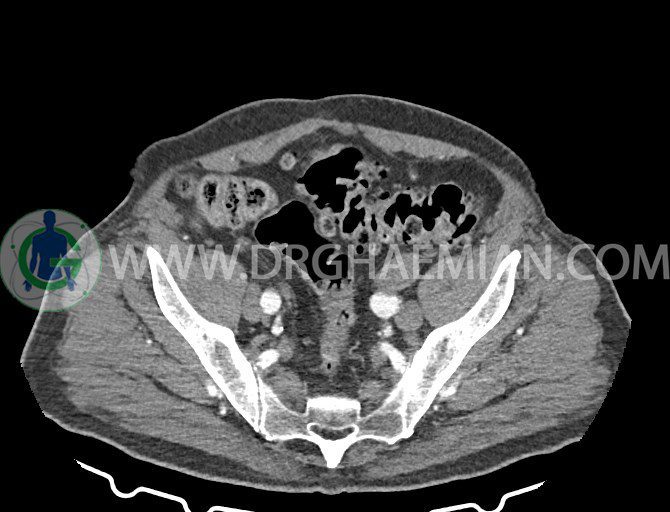

سی تی اسکن لگن یکی از روش های تصویربرداری با سی تی اسکن است. این روش با استفاده از تشعشعات تصاویر عرضی از ناحیه شکمی ایجاد میکند. در این کیس ديورتيكولوزيس، کیست های کورتیکال در هر دو کلیه، لنفادنوپاتی، کلسیفیکاسیون دیواره آئورت و شریان ایلیاک، تغییرات DJD ناحیه توراکولومبار و پروستات بزرگتر از عادی دیده می شود.

در سي تي اسکن اسپيرال شکم و لگن با و بدون کنتراست خوراکی و وريدی (مولتي ديدکتور 16 با مقاطع ظريف و بازسازي هاي ساژيتال و کرونال):

– کلسيفيکاسيون ديواره آئورت و شريان ها ايلياک همراه با نشانه هاي ترومبوز مورال در بيفورکاسيون ائورت با امتداد به پروگزيمال هاي شريان هاي ايلياک

– ديورتيكولوزيس در کولون نزولي وسيگموئيد

لنفادنوپاتي به ابعاد mm 22 x 25 مجاور شريان ايلياک خارجي چپ و به ابعاد mm 17 x 28 مجاور شريان ايلياک خارجي راست

– پروستات به ابعاد mm 45 x 54، بزرگ تر از نرمال

مشهود است.